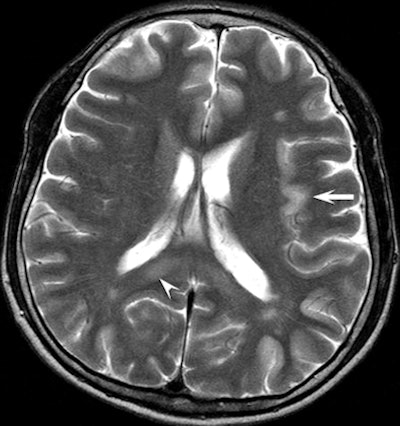

Above is a T2-weighted MR image of bilateral patchy hyperintense lesions in the cerebral cortex, including the insula (arrow). There is also involvement of the splenium of the corpus callosum (arrowhead). On the corresponding diffusion-weighted MR image below, the hyperintense lesions are more prominent than above. |

In seven patients, there was cortical involvement that the authors described as "patchy noncontiguous" in four cases and "confluent" in three patients, with sparing of the subcortical white matter and cerebellum. Three patients displayed abnormalities of the splenium of the corpus callosum in addition to the cortex.

"These findings are consistent with those of previous studies that described selective vulnerability of the brain to hypoglycemic damage and characteristic lesion distribution," the authors wrote.